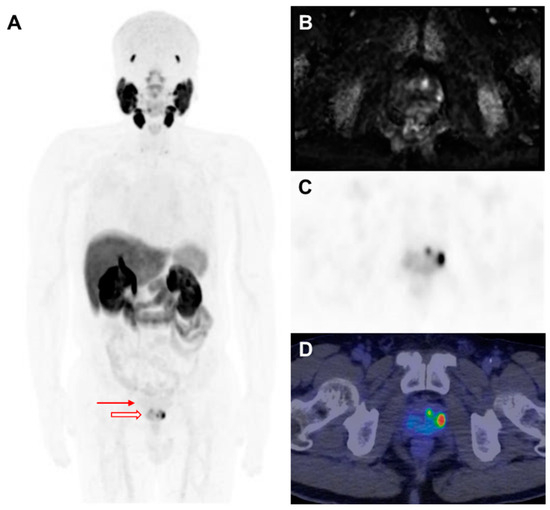

- Giesel, F.L.; Kesch, C.; Yun, M.; Cardinale, J.; Haberkorn, U.; Kopka, K.; Kratochwil, C.; Hadaschik, B.A. F-18 PSMA-1007 PET/CT Detects Micrometastases in a Patient With Biochemically Recurrent Prostate Cancer. Clin. Genitourin. Cancer 2017, 15, e497–e499. [Google Scholar] [CrossRef]